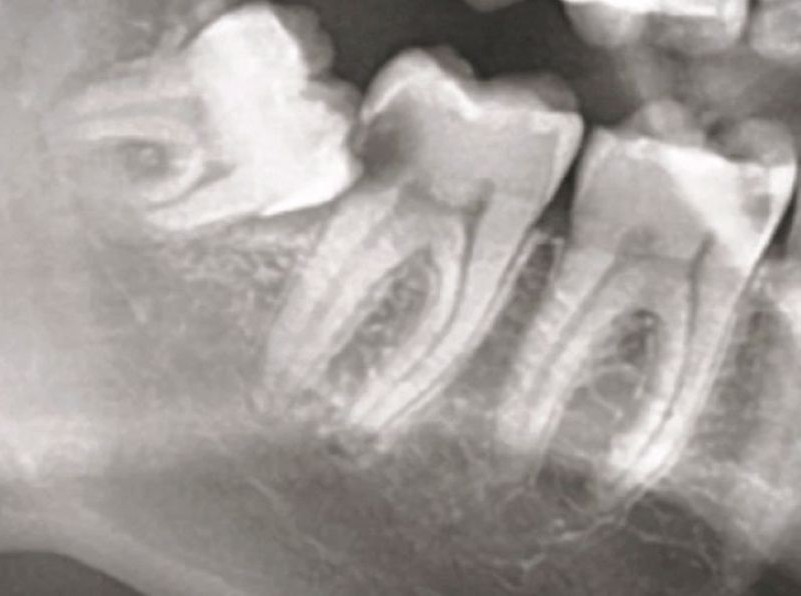

Ендодонцијата е гранка на стоматологијата која се занимава со третман и превенција на болести и состојби што ја зафаќаат забната пулпа и околните ткива. Забната пулпа е меко ткиво во внатрешноста на забот, составено од нерви, крвни садови и сврзно ткиво. Ендодонтскиот третман најчесто подразбира терапија на коренскиот канал, чија главна цел е да се спасат забите кои се сериозно оштетени или инфицирани.

Терапијата на коренскиот канал е најчестата ендодонтска процедура. Процесот вклучува:

Во одредени случаи, кога конвенционалниот третман на коренскиот канал не е доволен, може да се изведе ендодонтска хирургија. Најчеста процедура е апикотомија — хирургија на врвот на коренот, при што се отстранува врвот на коренот заедно со инфицираното ткиво. Овој процес помага да се елиминира изворот на инфекцијата и да се зачува забот.